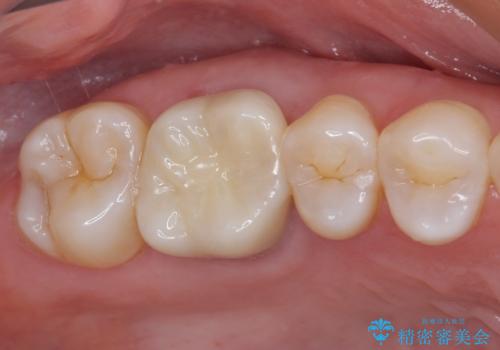

- 上下の奥歯に違和感を感じ、近医にて虫歯を指摘されたとのことで来院された患者様です。

診査したところ、下顎の奥歯は膿の出口ができており、上顎の奥歯は噛んだときに痛みを感じている状態でした。

まずは根管治療を行い、症状が落ち着いたことを確認して、オールセラミッククラウンにて補綴治療を行うこととしました。

処置後、下顎の膿の出口はすぐに消えましたが、レントゲン写真からも分かるとおり、歯根途中に穴が開いており、充填材が歯根外にはみ出していました。数ヶ月経過を見たところ、特に異常は認められなかったため、補綴治療を行いました。